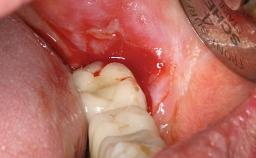

Peripheral Giant-cell Granuloma Associated with Peri-implant Tissues

Giant-cell granulomas (GCG) of the jaws are benign reactive lesions of unknown etiology, unrelated to giant-cell tumors (osteoclastomas), which are defined as benign but locally destructive and aggressive neoplasms (Jundt and coworkers 2005). Depending on their localization at the initial diagnosis, GCG are dived into central (CGCG) and peripheral (PGCG) types. CGCGs occur within the jawbones and appear as unilocular or multilocular radiolucent lesions. The incidence in the general population is very low. They are more commonly found in the mandible, mainly in children and young adults—patients are generally younger than 30 years—and have a greater incidence in females (Heithersay and coworkers 2002). The clinical behavior of CGCGs varies from slowly growing asymptomatic swellings to aggressive lesions that may result in pain, cortical perforation of the affected jaw site, and root resorption (de Lange and coworkers 2007).